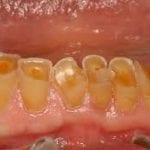

You may have significant enamel erosion if you experience pain, high sensitivity when exposed to cold, hot, acidic, and spicy food and drink, and discoloration in your teeth.

- yellow, stained teeth

- overly sensitive teeth

- increased tooth decay

- gradual wearing of enamel, leading to clear, slightly translucent teeth